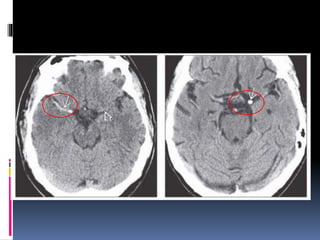

NECT shows hypodensity of the right basal ganglia compared to the normal.

pCT was performed CBV shows markedly reduced blood volume in the right basal

ganglia compared to the normal left side .

CBV in the cortex overlying the basal ganglia infarct appears relatively normal.

NECT shows hypodensityof the right basal ganglia compared to the normal. pCT was performed CBV shows markedly reduced blood volume in the right basal ganglia compared to the normal left side . CBV in the cortex overlying the basal ganglia infarct appears relatively normal.